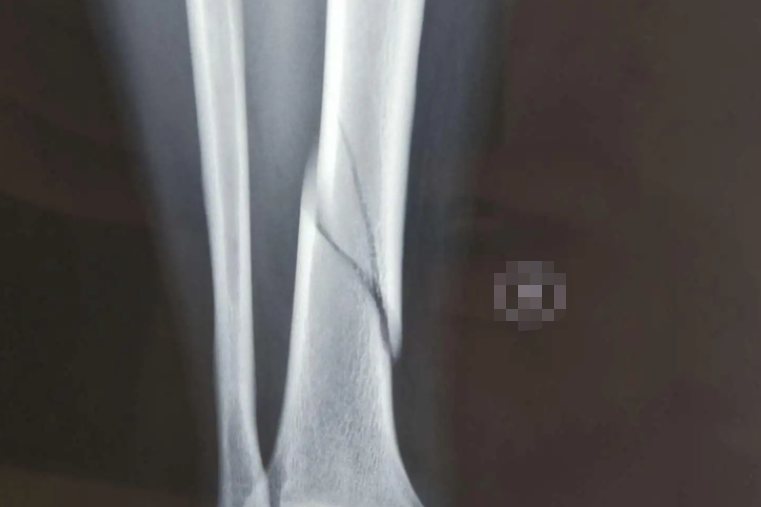

螺旋形骨折造成的骨折移位明显、不稳定,骨折断端可以穿破皮肤,形成开放性骨折。患肢会出现较为明显的旋转、短缩畸形。骨折部位的软组织损伤通常较为严重,因此出现明显的肿胀、疼痛感觉。X光片或CT下可以看见明显的螺旋形骨折线。

大部分螺旋形骨折患者因为骨折移位明显,外固定难以恢复其原有的解剖结构,通常需要进行手术切开复位内固定,有利于患肢的愈合,以及功能的恢复。若是没有明显移位的患者也可以采用外固定治疗。